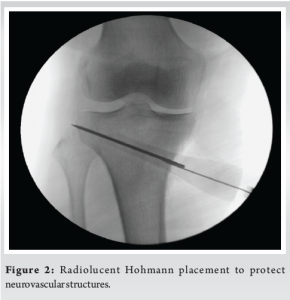

A 56-year-old female was diagnosed with medial compartment osteoarthritis (Kellgren-Lawrence grade 3) with varus malalignment (Fig. 1a) and medial meniscus posterior root tear. The patient was planned for arthroscopic medial meniscus root repair and MOW-HTO. The planned correction angle was 8.5° with opening wedge thickness of 9 mm (Fig. 1c). Meniscus root was repaired with a suture anchor. For the osteotomy, a small vertical incision was taken over the medial aspect of the proximal tibia below the joint line and midway between anterior and posteromedial margins of tibia. The pes anserinus tendon was identified and superficial medial collateral ligament (sMCL) partially released at that level. A radiolucent Hohmann retractor was strategically placed from under the released sMCL going posteromedial to protect the neurovascular structures. The Hohmann was placed obliquely all the way along the osteotomy line which was directing toward the tip of fibula under fluoroscopy guidance (Fig. 2). Osteotomy path was positioned using 2 K-wires starting just above pes anserinus level at the medial metaphyseal flare of tibia aiming toward the tip of fibula. Once sure, osteotomy was done was oscillating saw and opened using “3 chisel technique.” The correction was planned using Miniaci technique at Fujisawa point, i.e., 62% of tibial plateau as measured from medial side (Fig. 1b). Care was taken to maintain the lateral hinge. The open wedge was filled with tricalcium phosphate (TCP) bone substitute toward the cortex to prevent post-operative collapse and loss of correction. Osteotomy site was secured with locking TOMOFIX plate. Drilling for screws was done carefully not to cross far beyond the distal cortex. The TCP and the plate were purposely kept postero-medially and fixed in knee extension to maintain the posterior tibial slope angle. The procedure was uneventful. On post-operative day 1, the patient complained of decreased sensation over the posterolateral area of leg and sole of foot along with generalized tingling in the lower limb with inability to flex the great toe (Video 1a). Rest of the neurovascular examination was normal. Post-operative X-rays showed good fixation with no protruding hardware. Magnetic resonance imaging of lumbosacral spine was done which showed mild disc bulge at L4-L5 and L5-S1 with no nerve compression or canal stenosis. This could not be related to patient’s symptoms. Nerve conduction velocity (NCV) test was done at 3 weeks which showed right tibial nerve injury pattern around knee level with moderate axonotmesis (Fig. 3a). Since the nerve was in axonotmesis, a conservative trial with a close follow-up was planned for the patient. The patient was given electrical stimulation therapy, interferential current therapy, physiotherapy, and pregabalin course. On 2-month follow-up, there was no pain. The patient was mobilizing full weight bearing. However, there was no neural recovery clinically. On 4-month and 1-year follow-up, great toe flexion power was 2/5 and there was a 50% subjective improvement in sensory complaints. The X-rays showed good progressive union (Fig. 4). Unfortunately, after this, the patient was lost to follow-up and came back to us after 5 years (6-year post-surgery). The patient had the osteotomy plate removed at another hospital. At this time, the patient had persistent paresthesia (subjectively around 40%) and great toe flexion was 4/5. The last follow-up is 14-year post-surgery where the motor function has recovered completely with some residual paresthesia (Video 1b).

MOW-HTO is known to be the safest among different types of HTO. It has become the osteotomy of choice for varus arthritis unless contraindicated. Some well-documented complications of this procedure are stiffness, implant failure, infection, thrombosis, and lateral cortex fracture [11,12]. Another technical complication is increase in posterior tibial slope angle which can cause future degeneration of anterior cruciate ligament [13]. Neurovascular injuries are the least common entities when it comes to MOW-HTO. Among the few reported neurovascular injuries, deep peroneal nerve (DPN) and popliteal artery are common. The DPN is a branch of common peroneal nerve which perforates the anterior intermuscular septum and runs between tibialis anterior and extensor muscles of the toe supplying them [14]. Cases of DPN injury during HTO have been reported in the past either due to protruding distal screws or trauma during drilling for the screws [15]. The popliteal artery lies anterior to the popliteal vein in the popliteal fossa making it the closest neurovascular structure while performing the osteotomy [16]. There have been reports of popliteal artery injury while using the saw during the osteotomy [17]. The tibial nerve being posterior to the popliteal vein naturally is the least likely to get injured [16]. Evidently so, till now, only one such case has been reported which was found out to be because of a long screw in the first distal screw hole [10]. Although nerve injuries are uncommon in MOW-HTO, one needs to have a thorough knowledge about the neurovascular structures around the proximal tibia [18]. Surgical steps need to be modified according to these anatomical considerations. Tibial nerve is the medial terminal branch of the sciatic nerve supplying the flexor muscles of ankle and toes including gasto-soleus, flexor hallucis longus, abductor hallucis, and the intrinsic muscles of the foot [14]. Its root value is L4-S3 and it gives cutaneous supply to the posterolateral part of leg, lateral foot, and sole of foot. In the leg, it passes over tibialis posterior and flexor digitorum longus in the midline, eventually passing under the flexor retinaculum and bifurcating into the lateral and medial plantar nerves. In this case, the symptoms were correlating to tibial nerve supply. Ruling out intervertebral disc herniation compressing the L5 and S1 root was important for documentation as peripheral nerve injury and lumbar disc herniation can mimic each other’s symptom [19]. The NCV revealed moderate axonotmesis which is characterized by disruptive lesion of the axon and its myelin coating. However, the anatomical shape of the nerve is preserved as the perineurium and epineurium are intact. These collagen coverings help the growth of axons during regeneration process, giving such injuries a good prognosis [20]. Thus, a conservative management with a close follow-up was decided for the patient. This included physiotherapy, electrical stimulation therapy, and pregabalin course. Physiotherapy comprised of mobilizing the scar and surrounding tissues, active muscle exercises to pump away the edema, massages to stimulate the muscles [21]. Partial weight bearing was started after 4 weeks and full weight bearing after 6 weeks of surgery. Electrical stimulation is known to enhance reinnervation and accelerate the axonal regeneration process in neural injuries [21]. Similarly, as concluded by Celik et al., pregabalin treatment in axonotmesis improves nerve regeneration by activating anti-inflammatory cytokine transforming growth factor beta-1 as evidenced in their histological studies [22]. Unlike the previously reported case, there were no protruding screws. The surgery was uneventful. There was no post-operative hematoma, the tourniquet time was well within normal bounds, there was no awkward patient positioning. With the help of the above points, a diagnosis of exclusion was reached to be of a stretch injury. The most logical reason for a stretch injury in this case was small size of incision needing excessive retraction. Peripheral nerves are known to get iatrogenic stretch injuries due to excessive and improper retraction. Antoniadis et al. in their study stated that osteotomy is one of the high-risk procedures and popliteal fossa is one of the high-risk sites for iatrogenic nerve injury [23]. Fig. 5 shows excessive stretching of soft tissues during retraction due to small incision, which might result in possible traction on tibial nerve while opening of the osteotomy with chisels. However, literature also says that tibial nerve is one of the least affected lower limb nerves by stretch injury. This is believed to be due to the larger size of the nerve, more numbers of fascicles, and higher amount of extra-fascicular tissue [24]. This further makes our case report a rare occurring. At 14-year follow-up, the patient still had partial residual paresthesia while the great toe flexion was recovered completely. She experienced discomfort on running or long-distance walking. This outcome coincides with a study by Retrouvey et al. which stated that even in cases of successful recovery of tibial nerve, most patients were unable to perform strenuous activities [25]. At this stage, the NCV also showed chronic tibial nerve injury which corroborates the residual paresthesia and discomfort. The author recommends a few awareness points during MOW-HTO. One of the most important and missed out factors is the length of the incision. In the race to keep the surgery minimally invasive, surgeons try to use smallest possible incisions. This creates the need for excessive retraction. As a result, there is an inadvertent pressure and stretch on the surrounding soft tissue which might be one of the major reasons of iatrogenic stretch injuries to peripheral nerves. In addition, a radiolucent Hohmann retractor should be placed vigilantly abutting the bone to avoid injury to the posterior neurovascular bundle. It is important that the plate is placed well posteriorly which not only maintains the posterior tibial slope but also avoids screw trajectory being too close to the important structures posteriorly. Knee should be flexed while performing the procedure pushing the vital structures more posteriorly. Thus, although MOW is the most reproducible type of HTO with least complications, a thorough knowledge about the surrounding soft tissue and related complications is paramount.